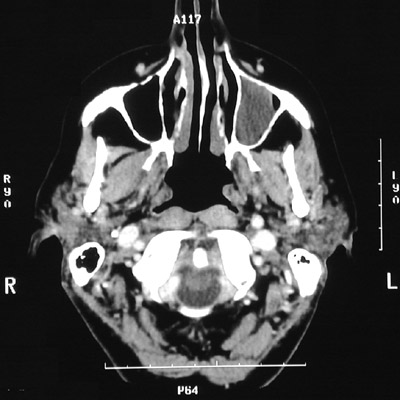

| Compared to the air-filled maxillary sinus on the right, the CT scans of the head above and below demonstrate a uniform gray appearance to the left maxillary sinus as a result of the collection of mucoid secretions following inflammation and stricture of the small duct draining the sinus. This is a mucocele that is expanding the sinus and thinning the surrounding bone. A mucus retention cyst from a blocked minor mucus gland in the paranasal sinus will appear similarly. |